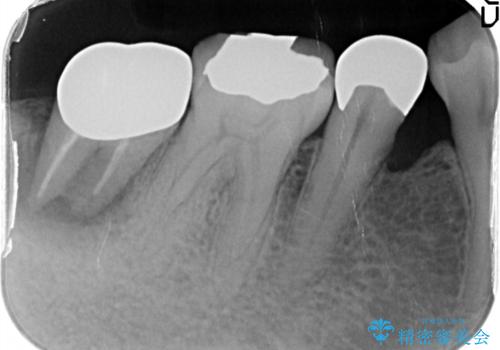

- 奥歯が痛いことを主訴に来院されました。

重度の歯周病により保存困難と診断し、抜歯後にインプラント治療を行いました。

抜歯後十分な骨の回復が認められず、単独の骨増生を行った後にインプラントを埋入しました。

インプラント埋入時に骨が足りない場合にはインプラント埋入前に骨増生を行います。また、インプラント周囲の角化歯肉が不足した場合は角化歯肉の移植も行うことがあります。